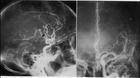

脉管瘤(vascular tumor)亦称管型瘤,或分别称血管瘤,淋巴管瘤;但有的脉管病变并非真性肿瘤故只能称脉管畸形(vascular malformation)。系来源于血管或淋巴管的肿瘤或畸形。